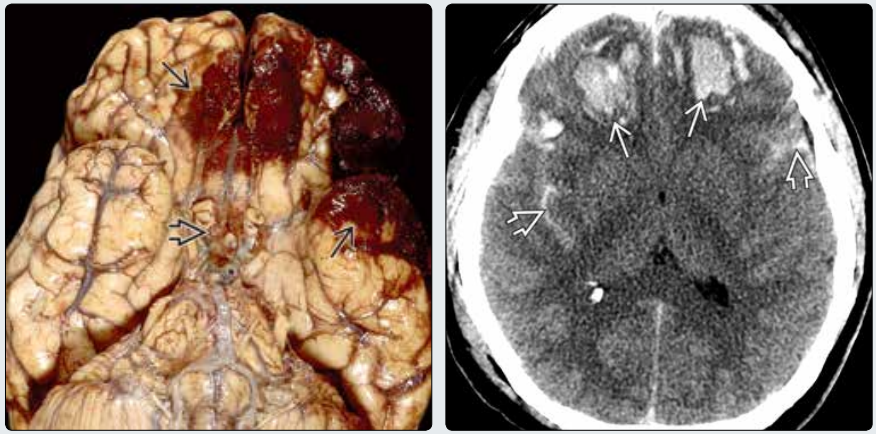

(左图)死于闭合性颅脑损伤的患者大体病理显示双侧额叶及颢叶脑挫伤出血→以及鞍上池➪的创伤性蛛网膜下腔出血(R.Hewlett, PhD.提供)

(右图)CT平扫显示严重脑外伤患者大范围的额颢叶脑挫伤→以及创伤性蛛网膜下腔出血➪